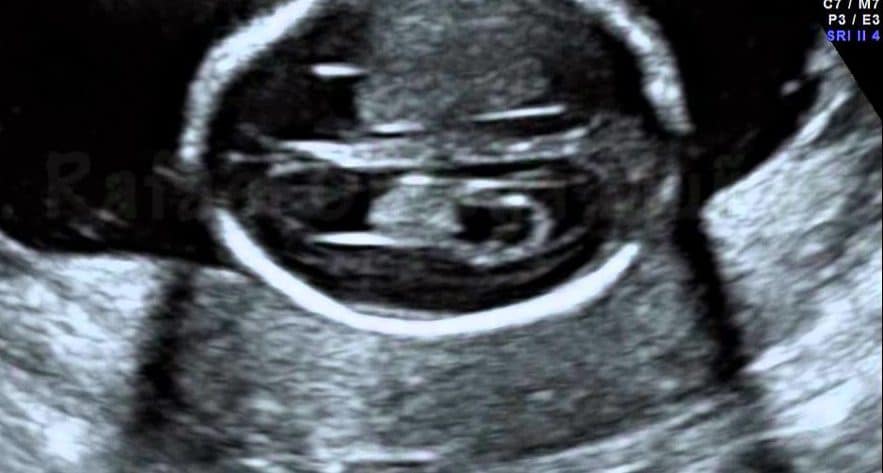

Ao ultrassom, os plexos coróides aparecem como estruturas hiperecogênicas (brilhantes, de alta refletividade) no interior dos ventrículos, visíveis bilateralmente a partir do primeiro trimestre. São uma referência anatômica importante na avaliação fetal entre 16 e 22 semanas de gestação.

Um cisto de plexo coróide se forma quando uma pequena quantidade de líquido fica aprisionada dentro do parênquima do plexo durante seu desenvolvimento. Ao ultrassom, aparece como uma área anecoica (escura, sem ecos) bem delimitada, com paredes finas e regulares, no interior da estrutura hiperecogênica do plexo.